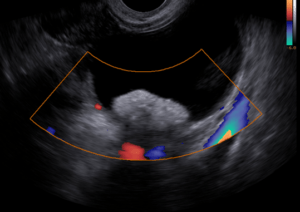

O diagnóstico do teratoma no ovário pode ser realizado sem dificuldades pelo ultrassom transvaginal.

Quando existir alguma dúvida quanto ao diagnóstico está indicada a ressonância magnética, mas na maior parte das vezes não é necessário.